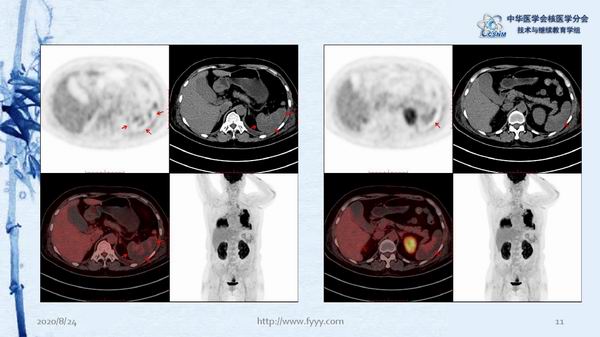

病例82:肉芽肿性血管炎PET-CT显像一例-【CSNM继教学组】郑山 福建医科大学附属第一医院